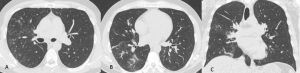

Figura 8: Donna di 62 anni con infezione da botulino e polmonite ab-ingestis. La TCAR eseguita all’ingresso al Pronto Soccorso (MPR coronale A e immagini assiali B e C) mostra la presenza di aree di aumentata densità con aspetto in parte consolidativo ed in parte a "vetro smerigliato" in entrambi i lobi inferiori e nella lingula con la presenza di stria atelettasica nella lingula.

Figura 9: Uomo di 65 anni giunto al Pronto Soccorso dopo aver rischiato la morte per annegamento. La TCAR eseguita all’ingresso (immagini assiali A-B-C e ricostruzione MPR coronale D) mostra la presenza di aree di aumentata densità con aspetto a "vetro smerigliato" in entrambi i polmoni con associato ispessimento liscio dei setti interlobulari con tipica distribuzione gravitazionale.